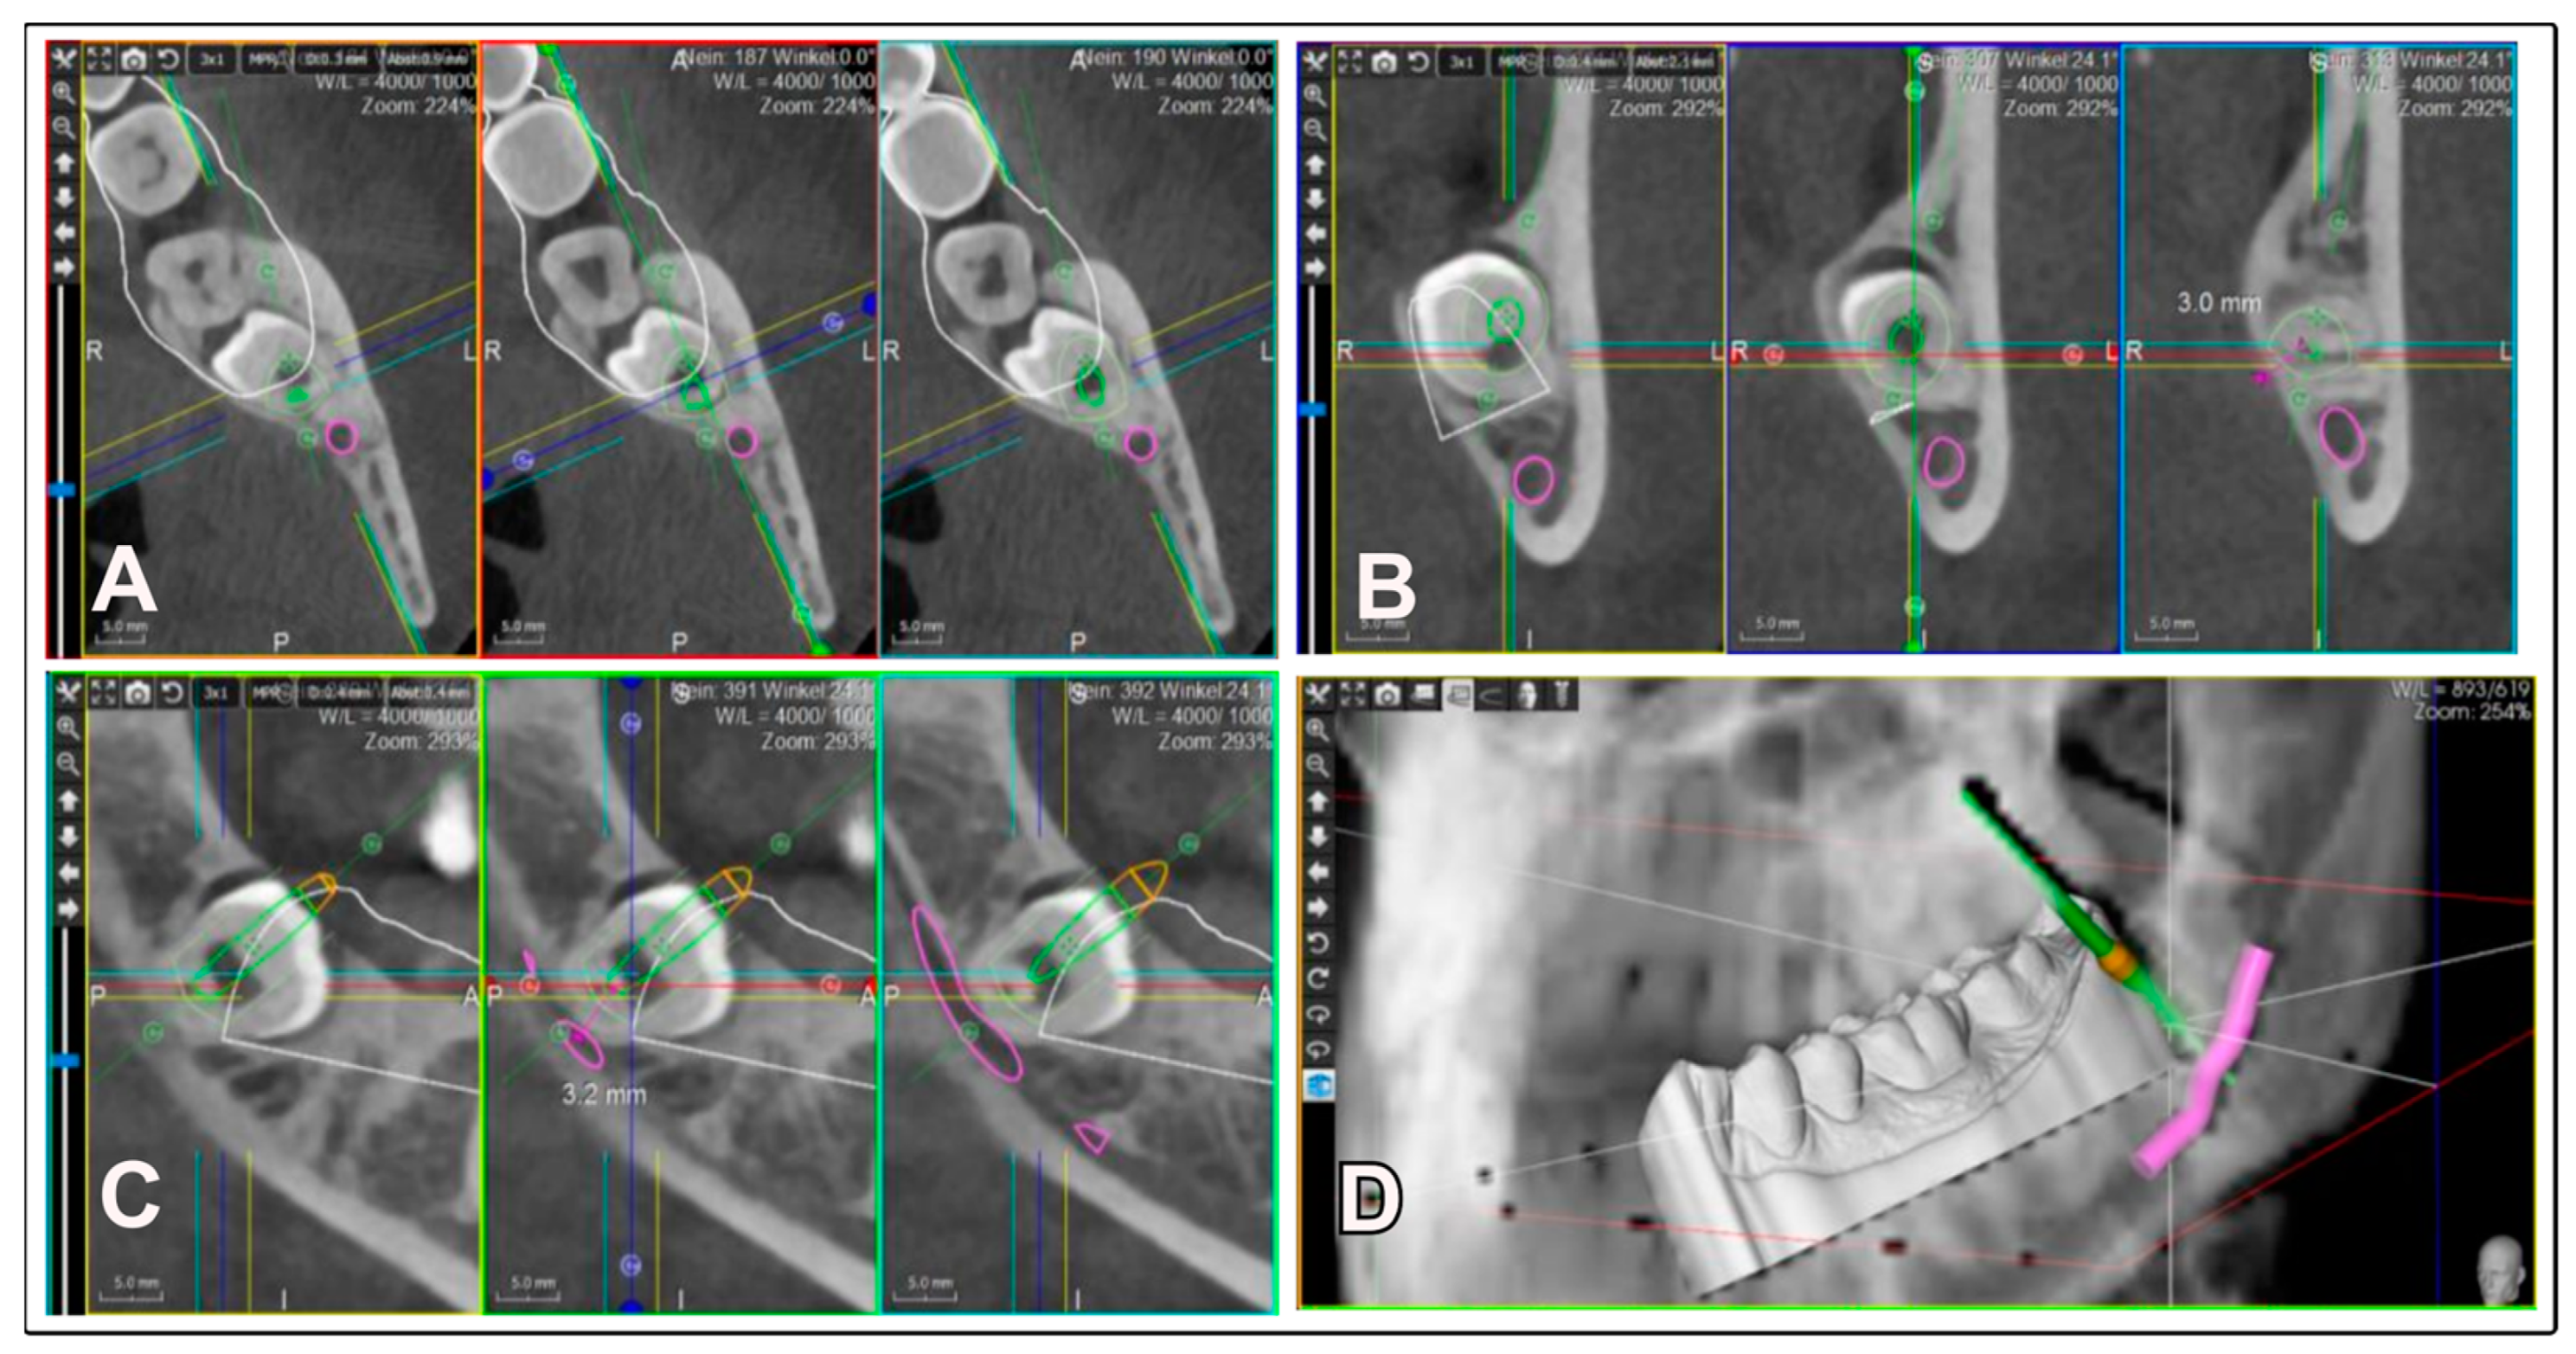

The patients had a close spatial relationship between the third molars and the IAN, as observed on the panoramic radiograph, necessitating a precise diagnostic assessment with a CBCT (WhiteFox, Acteon, France) at 105 kV and 10 mA with a 12 × 8 cm field of view (FOV). The images were reconstructed with a voxel size of 0.15 mm using WhiteFox Control software version 2.11.1 (WhiteFox, Acteon, France). Based on this CBCT examination (Figure 1), a 3D plan for minimally invasive removal was carried out.

Figure 1.

Three-dimensional planning of the surgical access for the IFT in CBCT. The target zone, i.e., the furcation area, is planned in three spatial planes: axial, coronal, and sagittal. (A): axial view, (B): coronal view, (C): sagittal view, (D): 3D representation of the direction and depth of the access to the furcation area.